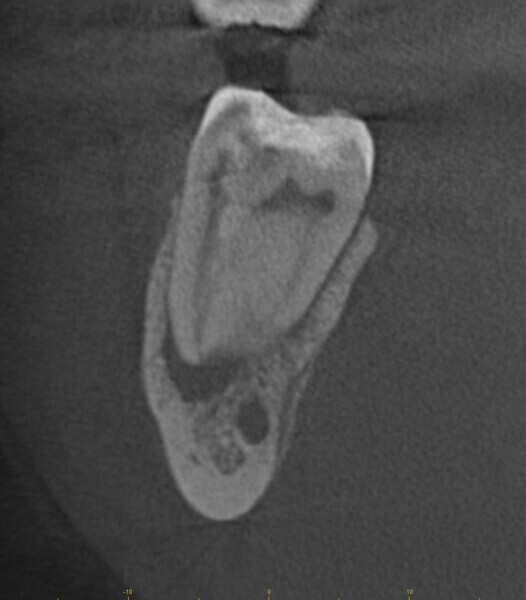

Fig. 17a: Case assisted with CBCT to determine anatomy pre-operatively. Note the multiple cross sections moving apically and the correlation to the 2-D view. Note also the conservative taper in relation to the root width. (Courtesy of Dr. Brett Gilbert)

Fig. 17b: Case assisted with CBCT to determine anatomy pre-operatively. Note the multiple cross sections moving apically and the correlation to the 2-D view. Note also the conservative taper in relation to the root width. (Courtesy of Dr. Brett Gilbert)

Fig. 17c: Case assisted with CBCT to determine anatomy pre-operatively. Note the multiple cross sections moving apically and the correlation to the 2-D view. Note also the conservative taper in relation to the root width. (Courtesy of Dr. Brett Gilbert)

Fig. 17d: Case assisted with CBCT to determine anatomy pre-operatively. Note the multiple cross sections moving apically and the correlation to the 2-D view. Note also the conservative taper in relation to the root width. (Courtesy of Dr. Brett Gilbert)

Fig. 17e: Case assisted with CBCT to determine anatomy pre-operatively. Note the multiple cross sections moving apically and the correlation to the 2-D view. Note also the conservative taper in relation to the root width. (Courtesy of Dr. Brett Gilbert)

Fig. 17f: Case assisted with CBCT to determine anatomy pre-operatively. Note the multiple cross sections moving apically and the correlation to the 2-D view. Note also the conservative taper in relation to the root width. (Courtesy of Dr. Brett Gilbert)